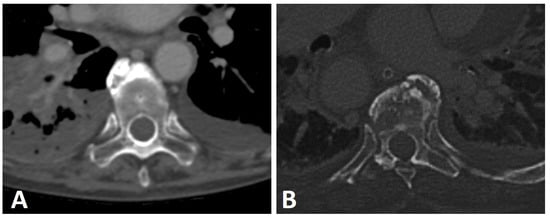

The chunky anterior cervical osteophytes in DISH are known to impinge upon the anteriorly located airways and esophagus and cause airway obstruction and dysphagia (Figure 3) [33], sometimes requiring surgical intervention [26,37].

Figure 3.

Axial CT image of a thick anterior osteophyte in the cervical spine of a patient with DISH that is impinging and causing narrowing of the adjacent esophagus (arrows).